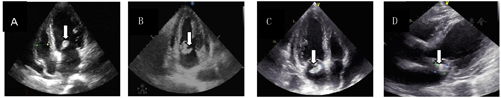

患者,男性,53岁,2022年3月14日因"胸闷1 d"求诊我院心内科,否认"冠心病、高血压、糖尿病"病史。入院体查:体温38.3℃,脉搏102次/min,呼吸22次/min,血压98/59 mmHg(1 mmHg=0.133 kPa),贫血貌,全身皮肤未见出血点,无指、趾甲下线状出血,无Olser结节、Janeway损害,双肺呼吸音粗,未闻及干湿啰音。心率102次/min,律齐,二尖瓣区收缩期闻及3级吹风样杂音,双下肢无水肿。辅助检查:心脏彩超:二尖瓣关闭不全,二尖瓣高回声结节,考虑赘生物(19.4 mm×11.7 mm,图1A),心电图:急性前壁心肌梗死。血培养:粪肠球菌,对青霉素、氨苄西林、万古霉素、替考拉宁敏感,高浓度庆大霉素MIC≦500 µg/ml。诊断:1.感染性心内膜炎;2.2型心肌梗死,予以万古霉素抗感染及对症支持治疗10 d后患者无胸闷,体温恢复正常,但复查心脏彩超赘生物较前进一步增大且血肌酐进行性升高,遂于2022年4月5日患者转入我科。

辅助检查:血常规:白细胞8.67×109/L,中性粒细胞7.45×109/L,血红蛋白60 g/L,血小板153×109/L,PCT 0.434 µg/L,CRP 111.1 mg/L,心肌酶:肌酸激酶200 U/L,乳酸脱氢酶377 U/L,肌红蛋白119.00 µg/L,心肌肌钙蛋白5.801 µg/L,BNP 5 784.00 ng/L,肝功能常规:白蛋白26.3 g/L,白蛋白/球蛋白0.70,肾功能常规检查:肌酐188 µmol/L,尿酸441 µmol/L,RF 119 .00 IU/ml,IgG 21.91 g/L。2022.03.18复查血培养:阴性。复查肾功能肌酐分别为160 µmol/L、177 µmol/L、198 µmol/L。复查肌钙蛋白分别为1.812 µg/L、0.750 µg/L、0.530 µg/L。复查心脏彩超赘生物大小分别为23 mm×12 mm、23 mm×18 mm(图1B、C)。

患者经"氨苄西林联合头孢曲松"抗感染过程中无再次发热,复查CRP进行性下降,分别135.1 mg/L,72.2 mg/L,27.9 mg/L,复查心脏彩超赘生物缩小至18 mm×17 mm(图1D)。复查肾功能肌酐进行性下降,分别为203 µmol/L、182 µmol/L、170 µmol/L。心胸外科会诊有紧急手术指征,患者及家属拒绝手术,患者再次突发胸闷伴有大汗淋漓,急查心电图:窦性心动过缓急性下壁心肌梗死,心肌酶正常,肌钙蛋白0.41 µg/L。心内科急会诊考虑赘生物脱落再次栓塞冠脉导致"2型心肌梗死",予以行急诊CAG+PCI+冠脉抽栓术,术后合并心源性休克转ICU治疗。复查肌钙蛋白3.796 µg/L,心肌酶:肌酸激酶4070 U/L、乳酸脱氢酶2078 U/L、肌红蛋白2019 µg/L。患者因心源性休克需持续血管活性药物维持,家属签字放弃治疗出院。进行电话随访患者死亡。